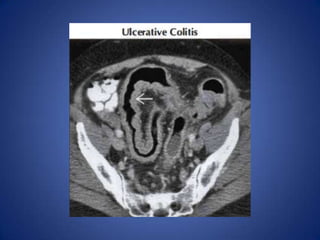

Ulcerative Colitis

• Favors rectum and distal colon

• Colonic wall is usually not very thickened

• Look for loss of haustral pattern, infiltration of

pericolonic fat

• Ask about history of prior episodes

Ulcerative Colitis • Favorsrectum and distal colon • Colonic wall is usually not very thickened • Look for loss of haustral pattern, infiltration of pericolonic fat • Ask about history of prior episodes